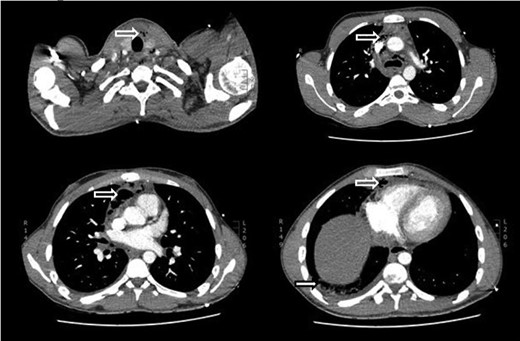

Initial laboratory investigations demonstrated: leucocytosis (11.8 × 109/l) with atypical lymphocytes; elevated C-reactive protein (346 mg/l); and elevated liver enzymes (alkaline phosphatase 147 IU/l, alanine aminotransferase 76 IU/l). Computed tomography imaging of the thorax and neck showed extensive pneumomediastinum with mediastinal fat stranding and pockets of fluid in the anterior mediastinum (Fig. 1). A small right pleural effusion, inflammatory consolidation in the right lung, reactive lymph nodes, splenomegaly and enlarged lymphoid tissue in the posterior nasopharynx were also noted. There was no evidence of oesophageal perforation; and peritonsillar or retropharyngeal abscesses were not present.

CT scan of neck and thorax showing mediastinal/cervical emphysema (hollow white arrows) and right empyema (solid white arrow).